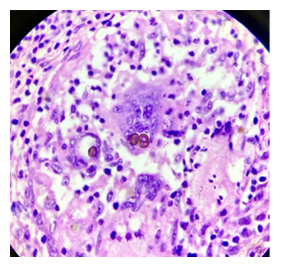

Pseudo-epitheliomatous hyperplasia, dermal infiltrate showing epithelioid granulomas, Acanthotic epidermis, ill-defined granulomas with Langans giant cells. Occasional cluster of thick walled, brownish spores/ sclerotic bodies were noted in the dermis 10% KOH mount: round, pigmented sclerotic bodies or “Medlar bodies”.

(Figure 5 & Figure 6)

Figure 5 10% KOH mount: Round, pigmented sclerotic bodies or “Medlar bodies”

Figure 6 Occasional cluster of thick walled: Brownish spores/sclerotic bodies were noted in the dermis